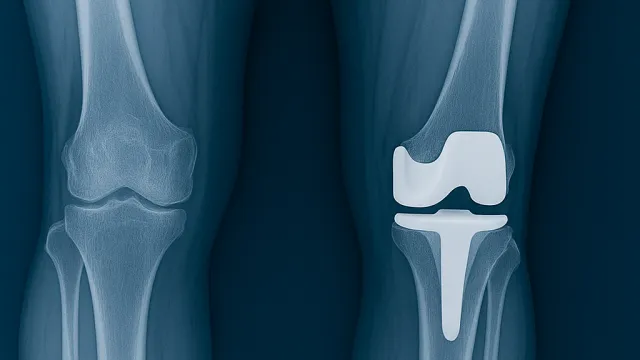

Artroskopik cerrahi, halk arasında “kapalı eklem ameliyatı” olarak bilinir. Küçük kesilerden ekleme yerleştirilen kamera ve özel aletler sayesinde eklemin içi net bir şekilde görülür ve sorunlu yapılar tedavi edilir. Bu yöntem sayesinde hem teşhis hem de tedavi aynı seansta yapılabilir.